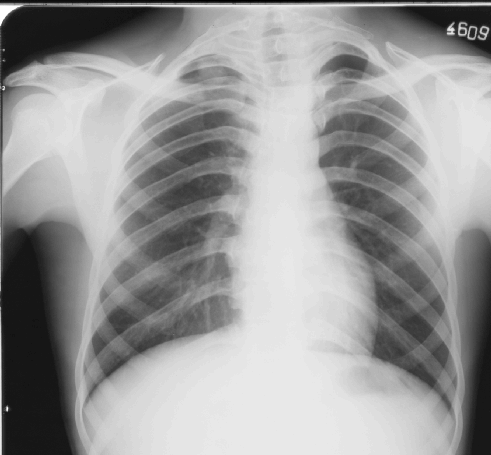

Radiografia del torace con proiezione postero-anteriore (radiografia convenzionale a film)